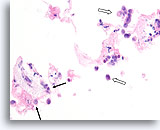

Lobulair neoplasie, Borst FNA, Celblok.

Een in-situ groeipatroon van lobulaire neoplasie is moeilijk of onmogelijk te identificeren in cytologische preparaten. Deze cluster van ongeveer 5 trossen is gedeeltelijk opgezet door het kenmerkende patroon van een losse ‘zak knikkers’ van lobulaire neoplasie zonder vorming van een glandulair lumen.

40X

Lobulair neoplasie, Borst FNA, Celblok.

Een in-situ groeipatroon van lobulaire neoplasie is moeilijk of onmogelijk te identificeren in cytologische preparaten. Deze cluster van ongeveer 5 trossen is gedeeltelijk opgezet door het kenmerkende patroon van een losse ‘zak knikkers’ van lobulaire neoplasie zonder vorming van een glandulair lumen.

40X

Lobulair neoplasie, Borst FNA, Celblok.

Een sterkere vergroting toont een kenmerkende targetoïde cytoplasmische vacuole (pijl)

100X

Lobulair neoplasie, Borst FNA, Celblok.

Een sterkere vergroting toont een kenmerkende targetoïde cytoplasmische vacuole (pijl)

100X